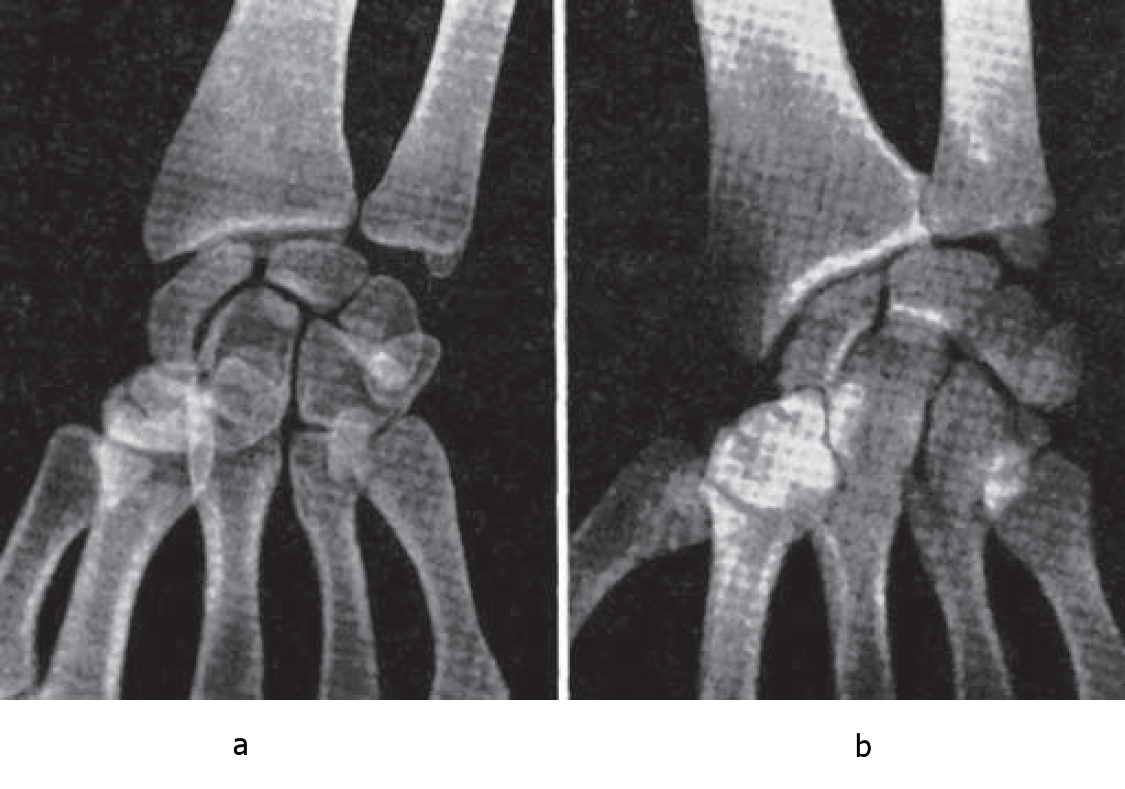

Two extreme types of carpal articulation are shown on Fig. 1. Herewith we have predicted the typical features of their articular surface and inhibitor structure since before the X-ray study – by the typical properties of their TPROM.

Fig. 1. Carpal articulation types. a – highly active (in master of sports in table tennis, 8-year experience); b – inactive (in road racer, honored master of sports, 18-year experience).

The closest correlation of form and function of joints is obvious. The game of a professional in table tennis is associated with the high quality and overwhelming number of so called “wrist shots”, which are fundamental for modern table tennis. The road racers hand (X-rayed in 1998) performs the static support function for many hours of trainings and contests, same as for foot while standing.

The schemes of these joints made basing on one-scale blueprints are shown on Fig. 2. The joint with the large scale of wrist abduction-adduction has a wide joint space (3 mm), weak congruence of articular surface of bones of proximal and distal rows (enlarged circumference of fossa). Small ulnar steloid and potential carpal bone rest point (3,5 mm) are spaced far (4,5 mm) apart. In the inactive joint articular surfaces are strictly congruent with the far narrower space between them (1,5 mm) and eccentric arch of articular surface of the lateral amplitude of 27 mm and medial – 45 mm. Ulnar steloid protrudes above caput ulnae for 6,5 mm and is nearly adjoining carpal bones.